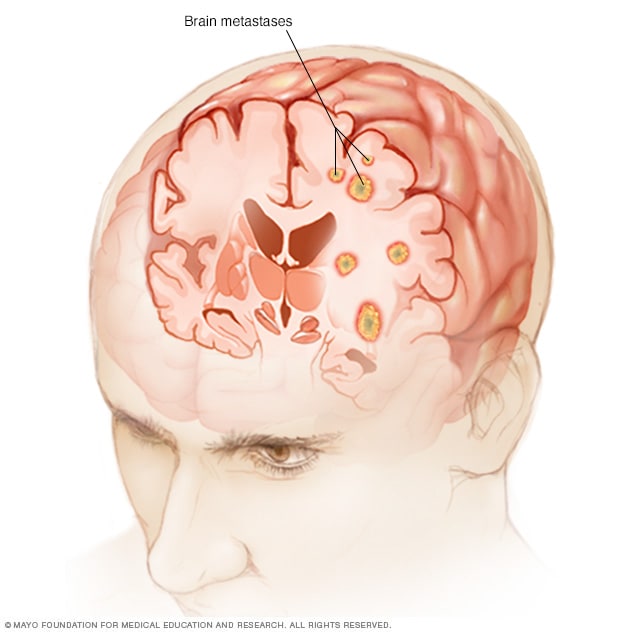

In adults, a secondary brain tumor, also called a brain metastasis, is much more common than a primary brain tumor.

About secondary brain tumors

A secondary brain tumor, or brain metastasis, is a cancerous tumor that started in another part of the body, such as the breast, lung, or colon, and then spread to the brain. A secondary brain tumor may also be called metastatic cancer. For instance, lung cancer that has spread to the brain may be called metastatic lung cancer.

If cancer spreads to the meninges and CSF, it is called leptomeningeal metastases or neoplastic meningitis. This condition occurs more commonly in people with leukemia, lymphoma, melanoma, breast cancer, or lung cancer.

When brain tumors happen in children, they're likely to be primary brain tumors. In adults, brain tumors are more likely to be cancer that started somewhere else and spread to the brain.

Cancer that spreads to the brain

Brain metastases

Brain metastases happen when cancer begins elsewhere in the body and spreads (metastasizes) to the brain.

Secondary brain tumors happen when cancer starts somewhere else and spreads to the brain. When cancer spreads, it's called metastatic cancer.

Any cancer can spread to the brain, but common types include:

- Breast cancer.

- Colon cancer.

- Kidney cancer.

- Lung cancer.

It's not clear why some cancers spread to the brain and others are more likely to spread to other places.

Secondary brain tumors most often happen in people who have a history of cancer. Rarely, a brain tumor may be the first sign of cancer that began somewhere else in the body.

In adults, secondary brain tumors are far more common than are primary brain tumors.